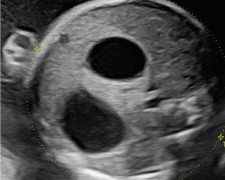

Casi del Mese di Dicembre 2024

Cari soci, finalmente on line le soluzioni dei casi del mese di Dicembre. Grazie a Sara Zullino e Mara Albanese!! Caso 1 - video [pdf-embedder url="https://www.sieog.it/wp-content/uploads/2024/12/Casodelmese_Dicembre2024caso-risposte_gineco.pdf"...